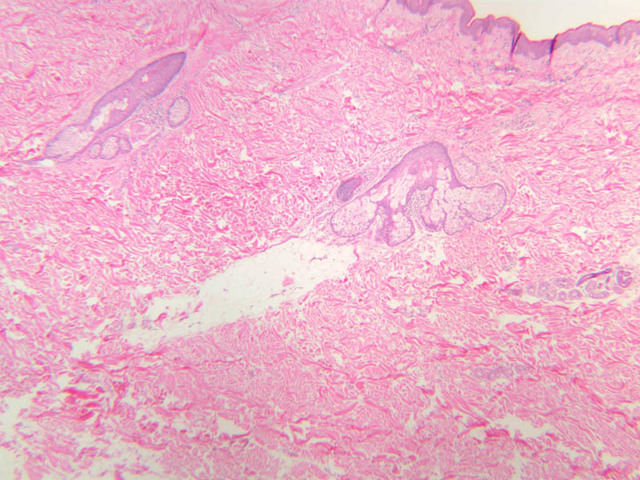

For general orientation, note that skin has two components, epidermis (a stratified squamous epithelium) and dermis (a connective tissue layer beneath the epidermis). Epidermal ridges project into the dermis, enclosing between them the highly vascular dermal papillae. Beneath the dermis lies the subcutaneous tissue, a loose layer of connective tissue, fat, blood vessels, and nerves. The skin appendages are situated partially in the dermis and partially in the subcutaneous layer. The skin consists primarily of two cell types; a keratin-producing epithelial cell (keratinocytes) and a pigment cell of neural crest origin (melanocyte). Langerhans cells are also present. These are believed to be antigen presenting cells of the epidermis. The keratinocytes exhibit morphological and functional stratification from base to surface of the epithelium and thus provide a basis for distinguishing several layers of the epidermis.

Examine slide A-50 (fingertip, H&E [2.5x, 10x-labeled, 20x, 40x-labeled] [20x, 40x] [10x, 20x, 40x] [20x, 20x, 40x]), and study the morphology of five layers of thick skin. The deepest part of the epidermis comprises the stratum basale which provides the cells required for continual renewal of the epidermis. This stratum is composed of a single layer of columnar or cuboidal epithelial cells attached to the basement membrane.

Superficial to the stratum basale is a multi-cellular layer known as the stratum spinosum, consisting of polyhedral cells that have a "prickly" or spiny appearance (A-50, langerhans cells [10x, 20x-labeled, 40x-labeled] [40x, 40x-labeled, 40x, 40x-labeled]; A- 48, abdominal skin, H&E [10x, 20x, 40x] [40x, 40x, 40x, 40x]). The spiny cells are separated by intercellular spaces that are bridged at numerous points by cytoplasmic processes, which in turn are bound together by desmosomes. The cytoplasmic processes projecting on all sides from the cells give them the spiny appearance to which the name refers. These are best seen under high power. Langerhans cells can also be found in this layer.

Superficial to the stratum spinosum is a layer of flattened cells with coarse, deeply-stained cytoplasmic granules, the stratum granulosum (slide A-50 [40x] [40x, 40x] [40x-labeled, 40x, 40x]). These are keratohyalin granules and evidently represent a stage in the keratinization of the epidermal cells. Note that the nuclei of the more superficial granular cells appear dense and pyknotic, foreshadowing their disintegration and the resultant death of the cells.

The stratum lucidum is often considered to be a subdivision of the stratum corneum. This layer is evident only in thick (glaborous) skin. It appears as a clear band beneath the stratum corneum. Cells of the stratum lucidum are well advanced in the process of keratinization. Consequently, the nucleus and many of the cytoplasmic organelles become disrupted and disappear as the cells become filled with the intracellular protein keratin. In many specimens, there is a separation artifact at this point. The outermost layer of the epidermis is called the stratum corneum and is composed of fully cornified (keratinized) remnants of epithelial cells ([40x]). It has a basketweave appearance. The close union of the resulting scales with each other, and their content of insoluble protein and extracellular lipids, provides a barrier to diffusion between the body and its external environment.